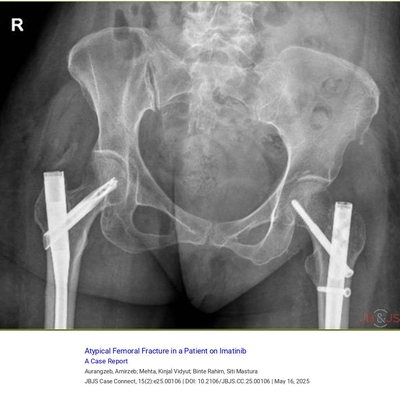

J Bone & Joint Surg

@the_jbjs